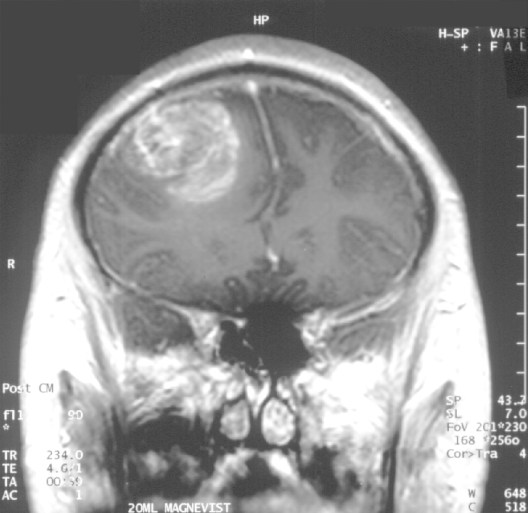

MRI image of high grade glioma brain tumor (white mass on left). Image: Wikipedia

The most aggressive forms of glioma are called high grade gliomas and they carry devastating prognoses. For instance, the most common form of these tumors in children has a median survival of just 9 months with a 5-year survival of less than 1%. Surgery or anti-cancer therapies may help for a while but the tumor inevitably grows back.